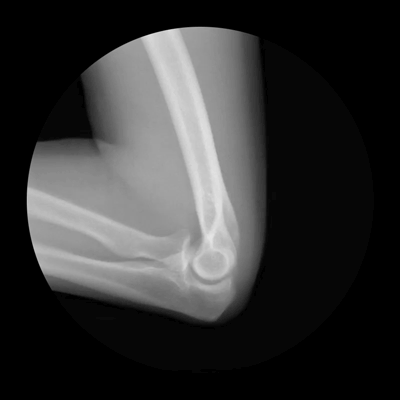

Elbow